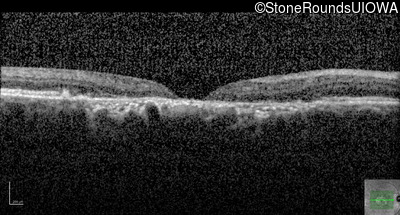

Pattern Dystrophy (IIC)

Age at visit: 47 years

This 47 year man first experienced some decrease in his central vision about 10 years ago.

Diagnosis & molecular findings

Pattern Dystrophy PRPH2 Gly167Asp GGC>GAC   AD